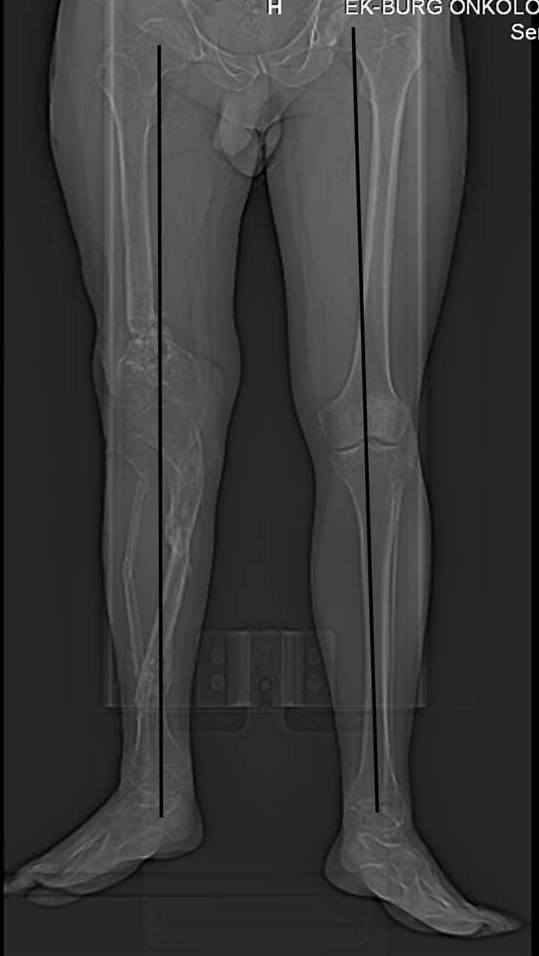

Псевдоартроз дистального отдела бедра. Distal femur nonunion (продолжение http://weborto.net/forum/1293474476/index_html)

Относительное укорочение - 6,1 см по КТ, осевую реконструкцию прилагаю (возможно не совсем корректная, но общее представление составить можно).